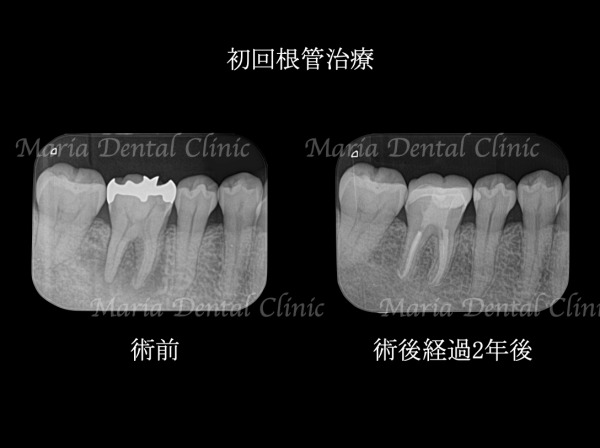

_術前術後の比較画像|目白マリア歯科-1024x758.jpg)